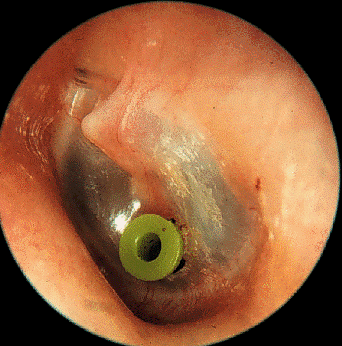

What are grommets cheap

What are grommets cheap, Grommets Mr Daniel Tweedie Consultant Paediatric ENT Surgeon cheap

What is a grommet ent4kids cheap, Grommets ENT Info cheap, Grommets Mr Daniel Tweedie Consultant Paediatric ENT Surgeon cheap, Grommets KidsHealth NZ cheap, Grommets KidsHealth NZ cheap, Description of operation for grommet ventilation tube insertion cheap, Grommets A decision making aid for parents ENT UK cheap, Grommets aarontrinidade cheap, Glue Ear Middle Ear Infections and Grommets Dr Sean Flanagan cheap, Ear Grommets ENT Clinic Sydney cheap, Grommets Adelaide Specialist ENT Surgeon Paul Varley ENT cheap, Ear Grommets ENT Clinic Sydney cheap, Grommets healthdirect cheap, Grommet Insertion Child Parkside Hospital cheap, Treatment of glue ear with grommets Great Ormond Street Hospital cheap, Grommets North View ENT Dr Sebastian Ranguis ENT Surgery cheap, Grommets Children s Health Queensland cheap, Grommets cheap, Grommets Ear Nose Throat Newcastle cheap, What are Grommets and how do they work Dr. Shalina Ray cheap, Grommets And The Benefits of Using Them cheap, Middle ear ventilation tubes grommets Dr Bridget Clancy ENT cheap, Grommets Mr Daniel Tweedie Consultant Paediatric ENT Surgeon cheap, Glue Ear Grommets Western ENT cheap, Grommet Insertion Surgery India Cost Grommet Insertion Surgery Abroad cheap, James Rainsbury Plymouth ENT specialist consultant Private cheap, How much does ear grommet surgery cost in Australia cheap, Grommets for glue ear treatment Essex London ENT cheap, Grommets Ear Nose Throat Newcastle cheap, Water precautions following grommets Dr Jeeve ENT Specialist cheap, All you need to know about grommets You cheap, Sydney Paediatric ENT Surgeon For Ear Grommets MY ENT cheap, Grommets MESHGuides cheap, Grommets aarontrinidade cheap, Grommets ENT Doctor Cape Town Dr Shabeer Ebrahim cheap.

What is a grommet ent4kids cheap, Grommets ENT Info cheap, Grommets Mr Daniel Tweedie Consultant Paediatric ENT Surgeon cheap, Grommets KidsHealth NZ cheap, Grommets KidsHealth NZ cheap, Description of operation for grommet ventilation tube insertion cheap, Grommets A decision making aid for parents ENT UK cheap, Grommets aarontrinidade cheap, Glue Ear Middle Ear Infections and Grommets Dr Sean Flanagan cheap, Ear Grommets ENT Clinic Sydney cheap, Grommets Adelaide Specialist ENT Surgeon Paul Varley ENT cheap, Ear Grommets ENT Clinic Sydney cheap, Grommets healthdirect cheap, Grommet Insertion Child Parkside Hospital cheap, Treatment of glue ear with grommets Great Ormond Street Hospital cheap, Grommets North View ENT Dr Sebastian Ranguis ENT Surgery cheap, Grommets Children s Health Queensland cheap, Grommets cheap, Grommets Ear Nose Throat Newcastle cheap, What are Grommets and how do they work Dr. Shalina Ray cheap, Grommets And The Benefits of Using Them cheap, Middle ear ventilation tubes grommets Dr Bridget Clancy ENT cheap, Grommets Mr Daniel Tweedie Consultant Paediatric ENT Surgeon cheap, Glue Ear Grommets Western ENT cheap, Grommet Insertion Surgery India Cost Grommet Insertion Surgery Abroad cheap, James Rainsbury Plymouth ENT specialist consultant Private cheap, How much does ear grommet surgery cost in Australia cheap, Grommets for glue ear treatment Essex London ENT cheap, Grommets Ear Nose Throat Newcastle cheap, Water precautions following grommets Dr Jeeve ENT Specialist cheap, All you need to know about grommets You cheap, Sydney Paediatric ENT Surgeon For Ear Grommets MY ENT cheap, Grommets MESHGuides cheap, Grommets aarontrinidade cheap, Grommets ENT Doctor Cape Town Dr Shabeer Ebrahim cheap.